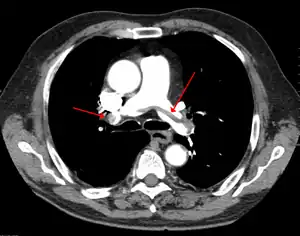

| Chest spiral CT scan with radiocontrast agent showing multiple filling defects both at the bifurcation ("saddle" pulmonary embolism) and in the pulmonary arteries | |

Segmental and subsegmental pulmonary emboli on both sides

CT pulmonary angiography showing a "saddle embolus" at the bifurcation of the main pulmonary artery and thrombus burden in the lobar arteries on both sides.